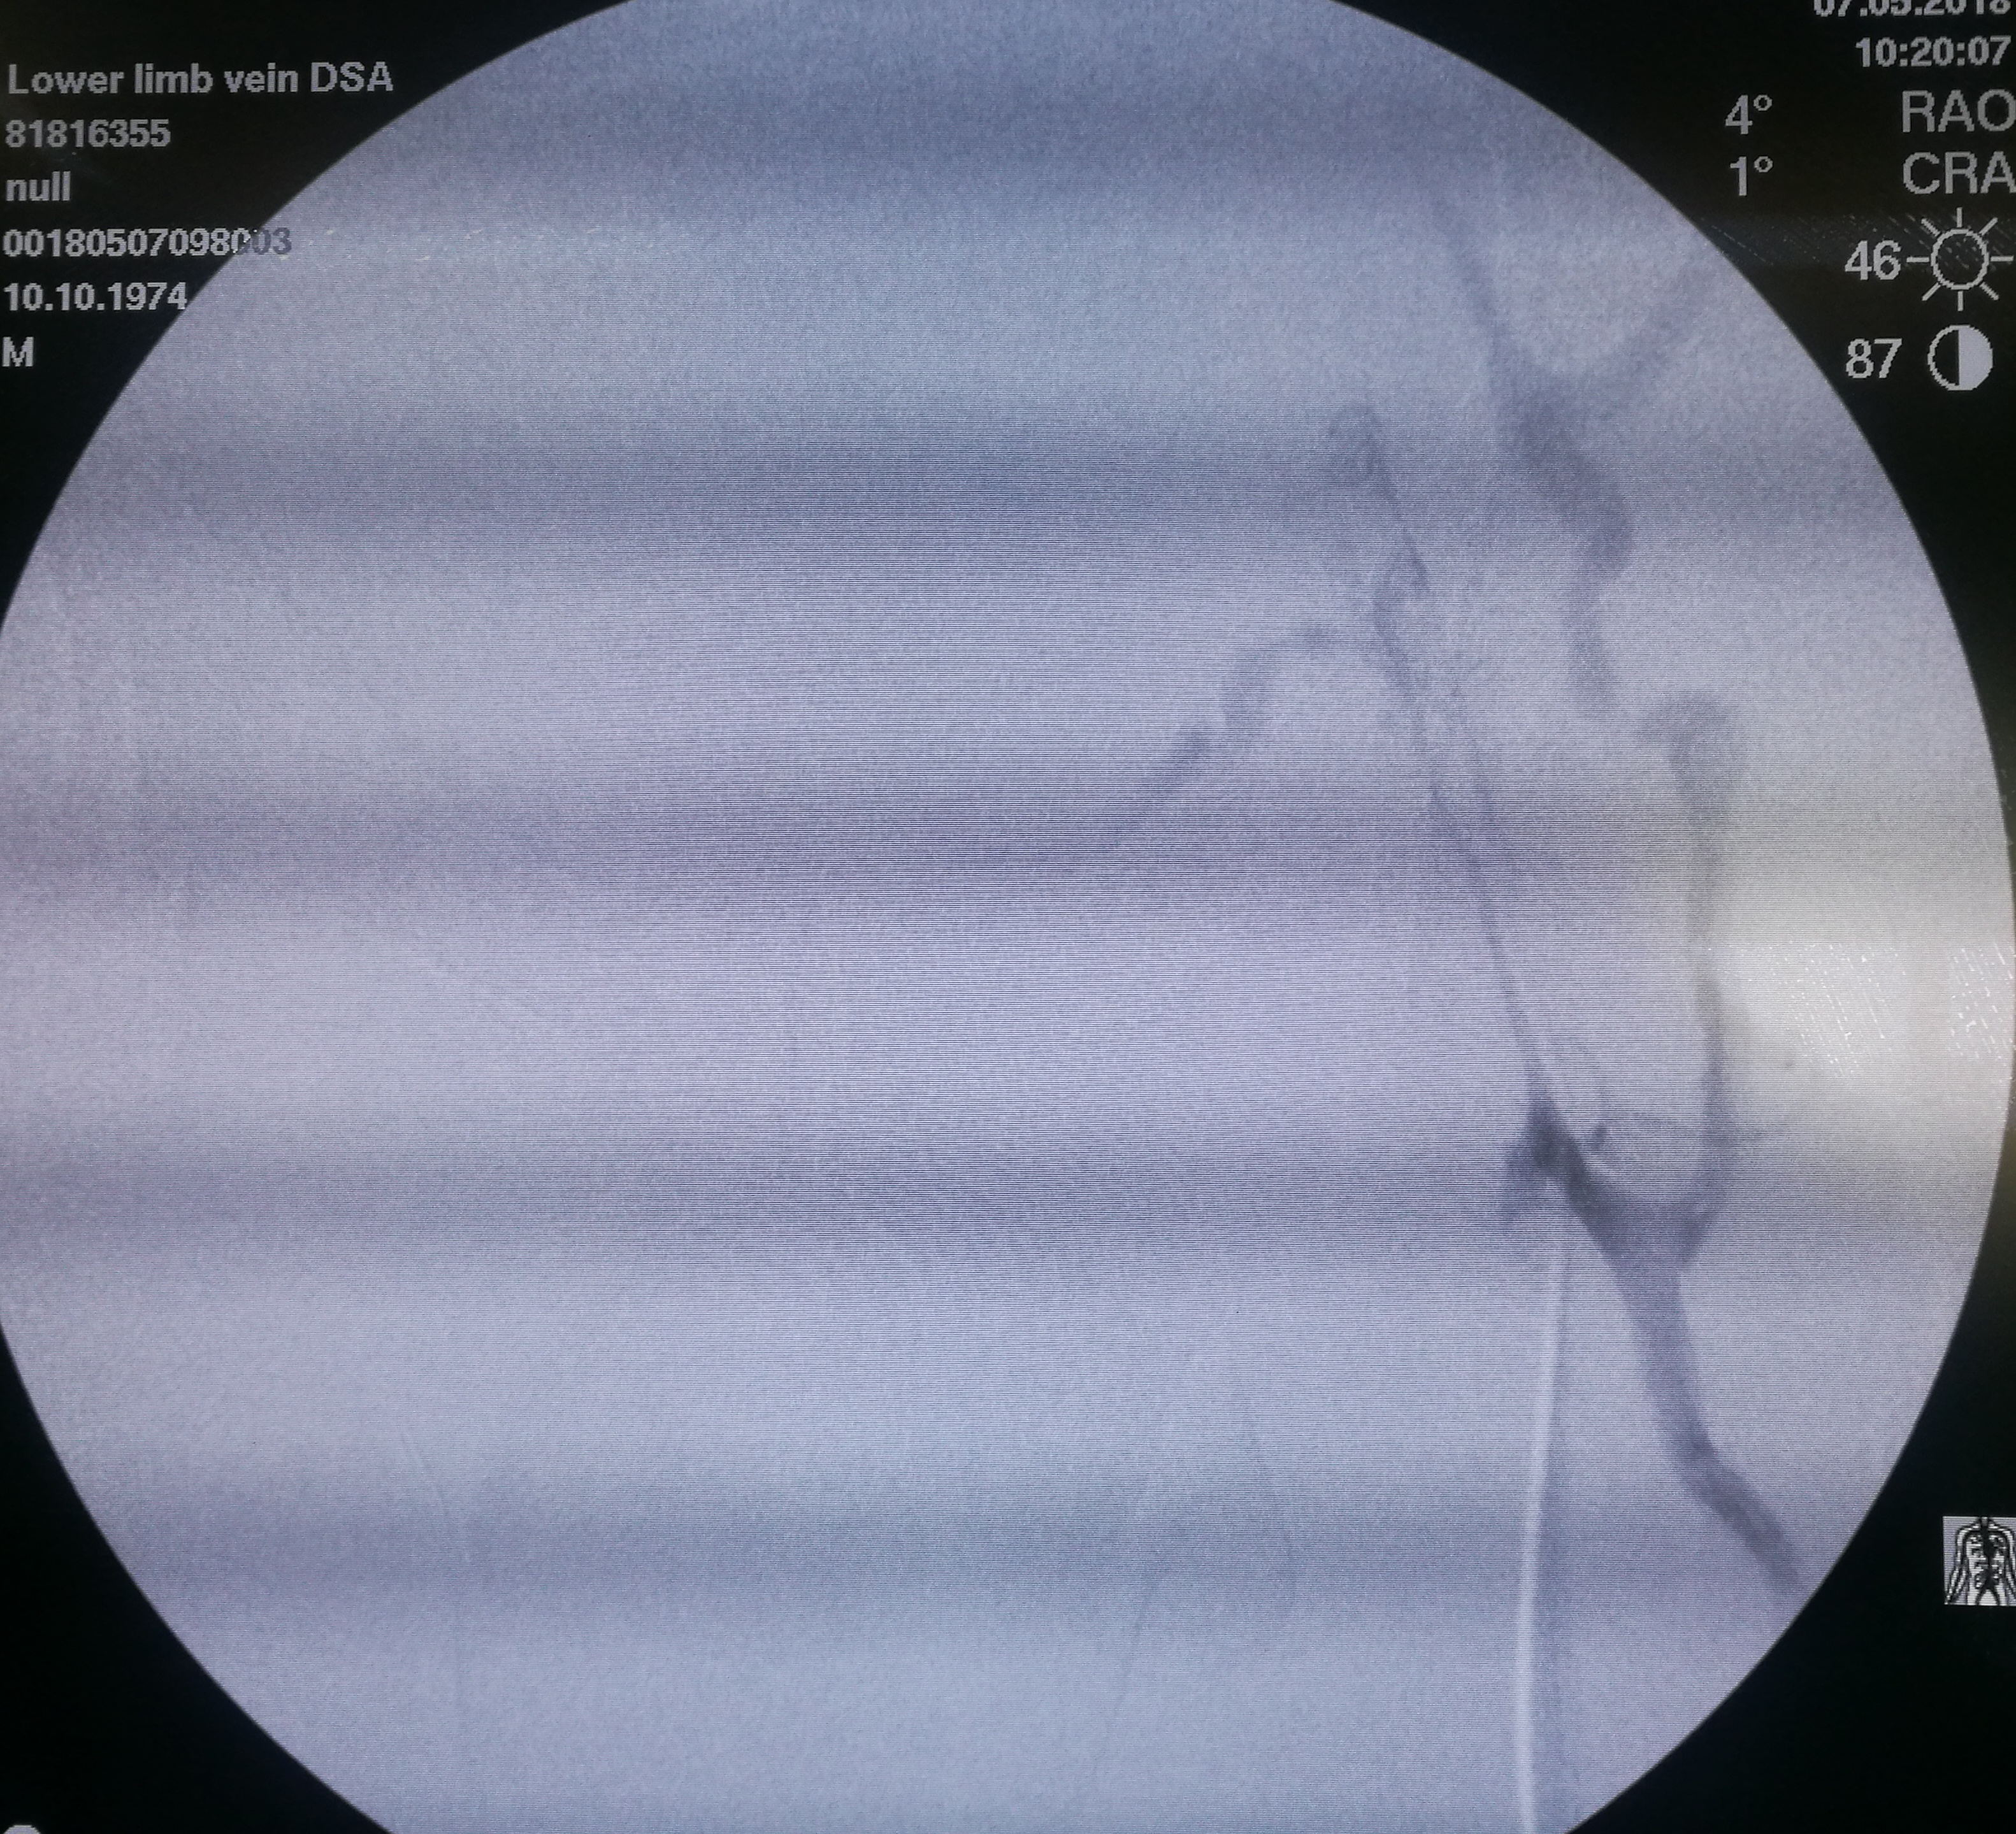

第三个患者是昨天做的,也是反复左下肢深静脉血栓,最近又发作。本次在超声引导下使用肝穿针穿刺左股静脉(其内充满血栓,盲穿无回血),配合超滑导丝,艰难前行约7-8cm后送入血管鞘,之后用导管导丝配合,进入到中线右侧,但从导丝头端的活动度看,未能回到下腔静脉。穿刺右侧股静脉,用SIM1导管从下腔静脉内逆行钩选左侧髂总静脉,在髂总远侧实现和左侧导管的对接,建立真腔轨道。之后在下腔静脉内植入滤器,再对左侧髂总、髂外静脉进行扩张,植入支架。

左髂静脉血栓闭塞

左侧导丝不能回到下腔静脉管腔内